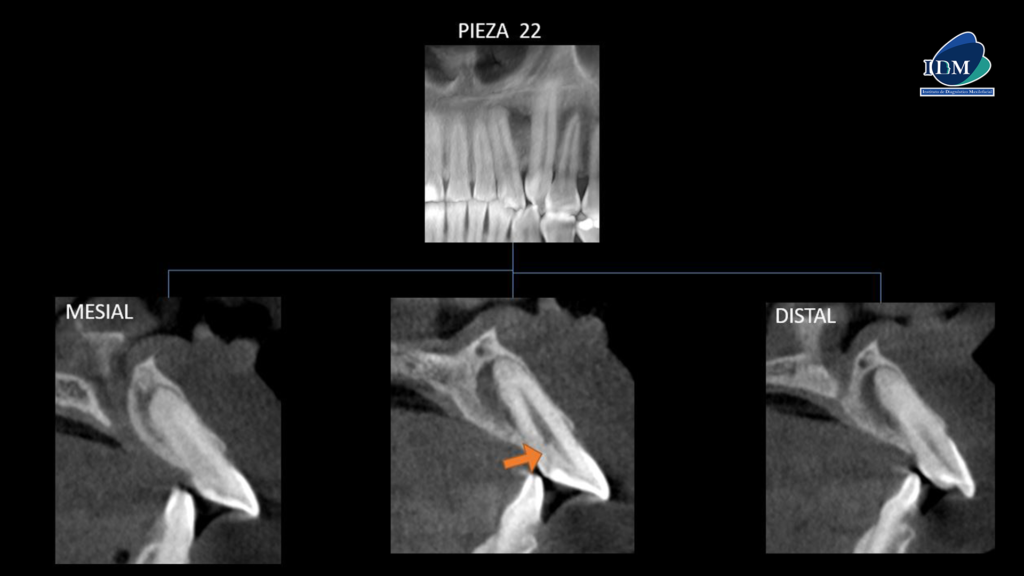

A la evaluación de los cortes transaxiales y tangenciales se observa la discreta invaginación de la pieza 22 (flecha naranja), así como el recorrido del canalisis sinuosus (flecha verde) y la presencia de la lesión osteolítico próxima a este.

CORTES TRANSAXIALES

CORTES TANGENCIALES